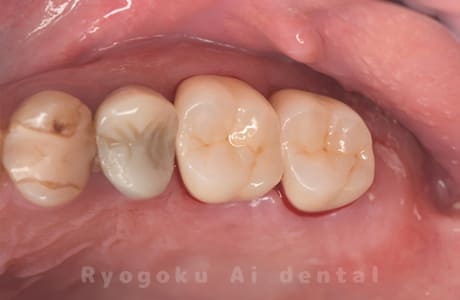

Case20

-

- 原因

- 重度カリエス

- 治療内容

- クラウンレングスニング

- 治療費用

- 44,000円

他院で抜歯と宣告され、当医院を受診された患者様です。クラウンレングスニングを行い、保存を行いました。経過良好です。

<リスク・副作用>

手術後は痛み、腫れ、痺れ、青あざなどの副作用が生じます。痛みは痛み止めを処方しますが、腫れ、青あざは1週間程度生じる場合があります。また、部位によっては神経の走行が複雑で、痺れが残り、長期的にお薬を処方する場合があります。